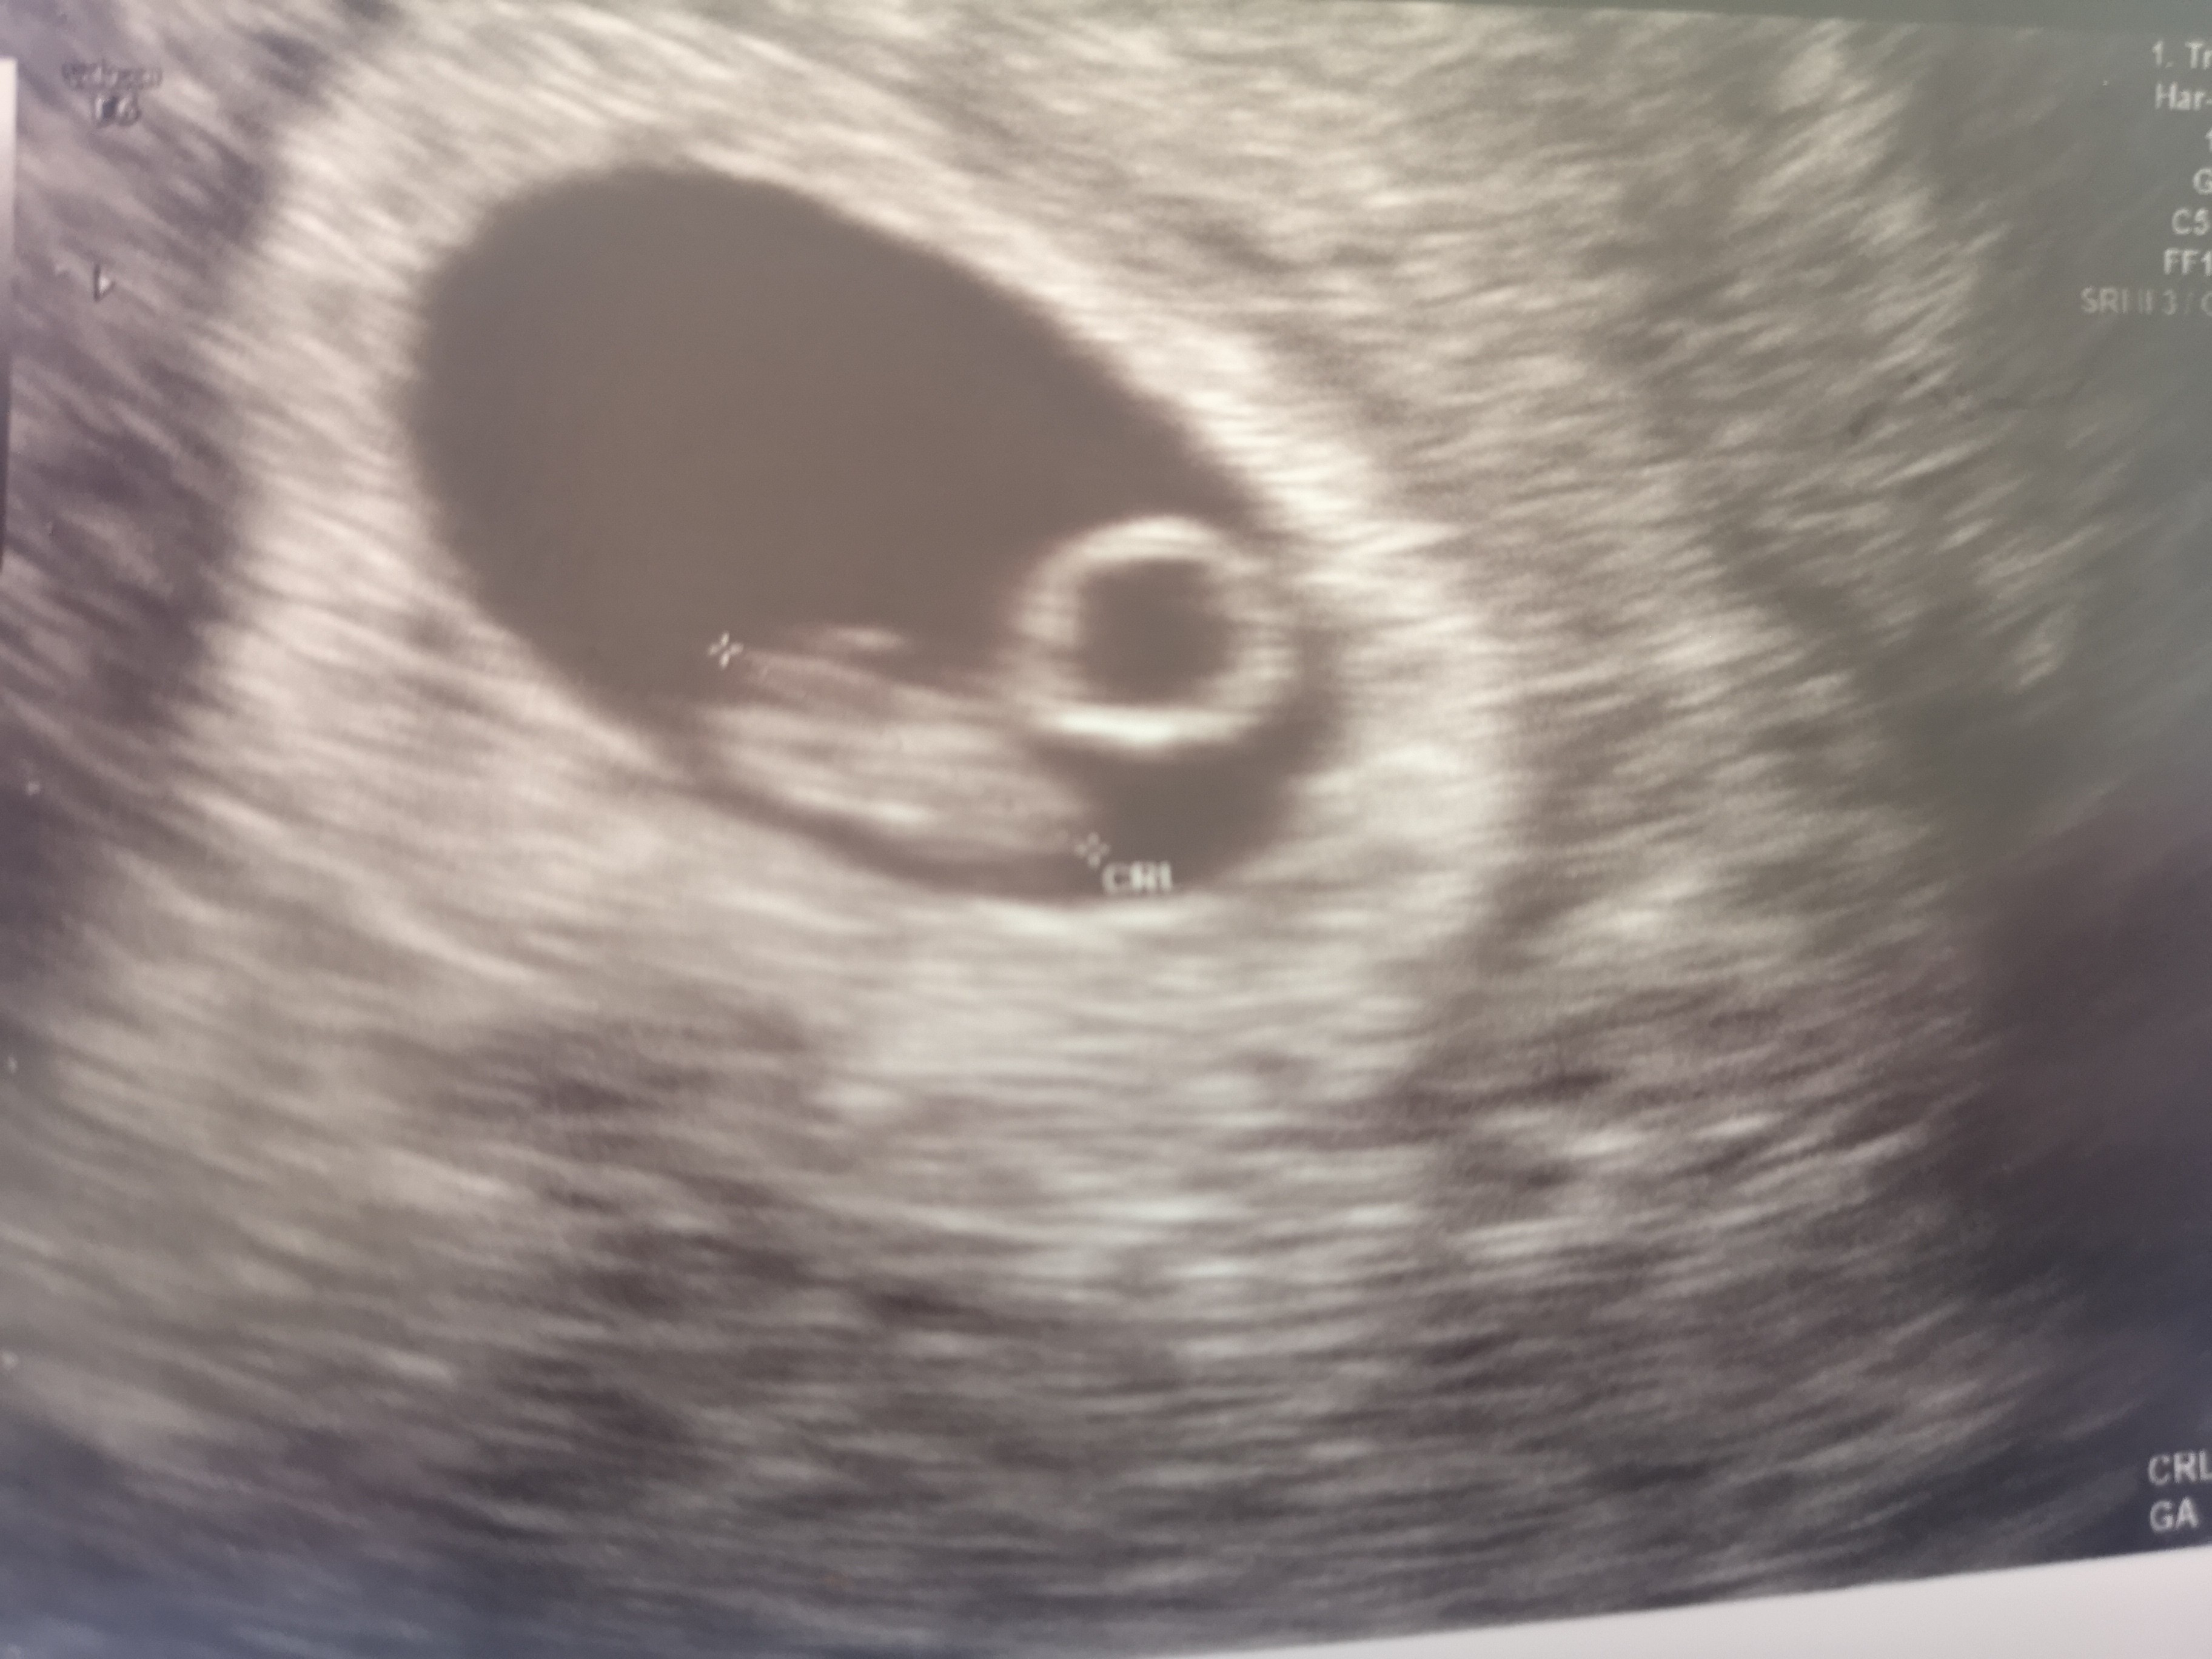

Ja juz po wizycie serduszko pięknie biło termin porodu 10 kwiecień 😊😍 troche mnie ta wizyta uspokoiła, dostałam tabletki na tw mdłości żebym mogła jakoś Chociaż funkcjonować 🤗

Załączniki

• IMG_20230821_145255.jpg

IMG_20230821_145255.jpg

1,1 MB · Wyświetleń: 73